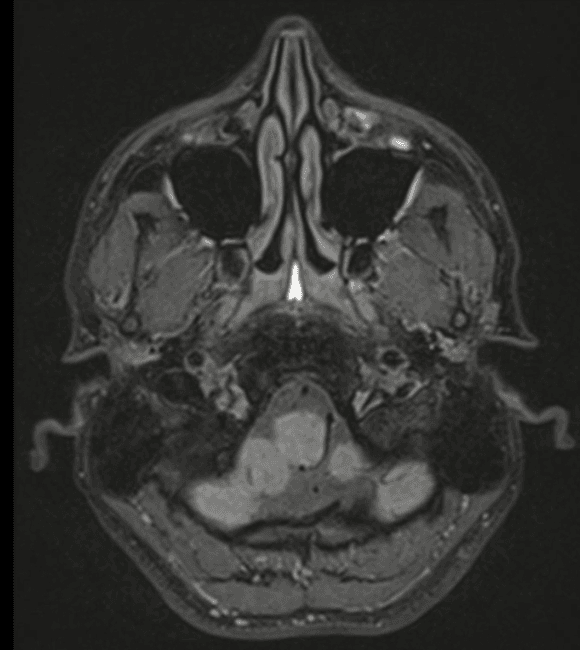

Nesta aula que fala sobre Hipertensão Intracraniana, Dr. Tomás Freddi discuti um caso clínico de relevância prática para clínicos e radiologistas: paciente jovem com cefaleia…